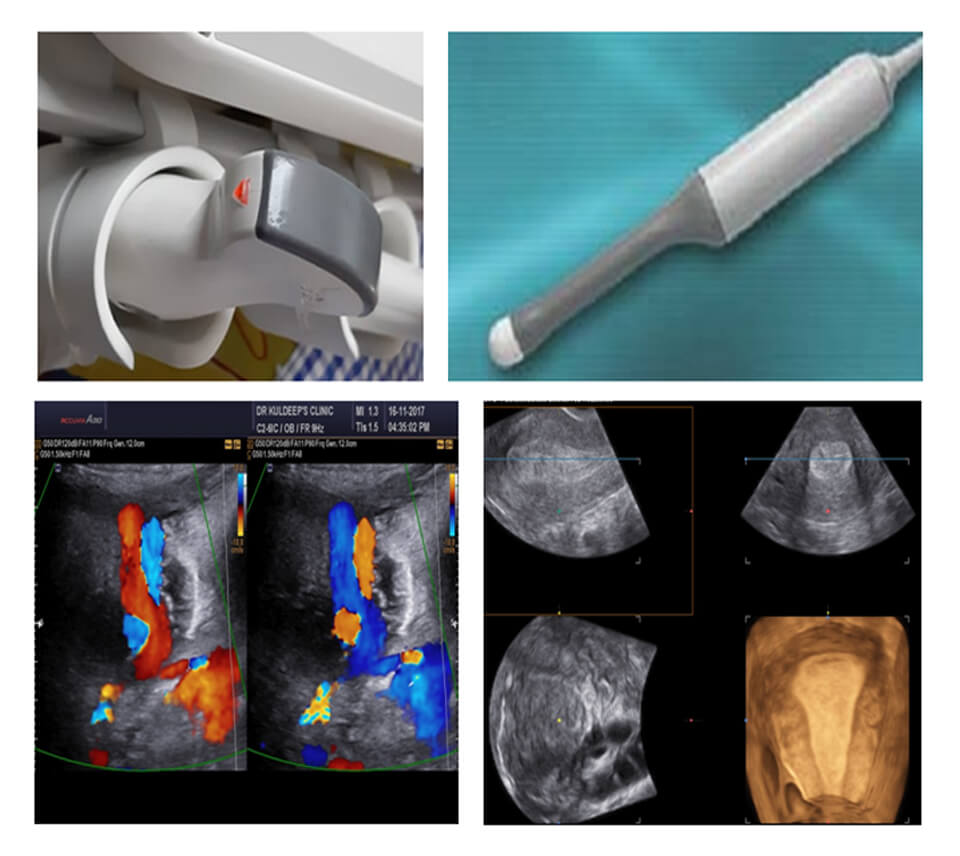

MODULE 1 :- KNOBOLOGY

2D KNOBOLOGY , PROBE MOVEMENTS, USG TERMINOLOGY, ARTEFACTS, SECTIONS, USG NOMENCLATURE, ORIENTATION, COLOR KNOBOLOGY, COLOR FLOW MAPPING, POWER ANGIO STUDIES, SPECTRAL DOPPLER, ANGLE CORRECTION AND INDICES, 3D/4D KNOBOLOGY, APPLLICATIONS, STEP BY STEP INSTRUCTIONS, ADVANCEMENTS AND CLINICAL USAGE